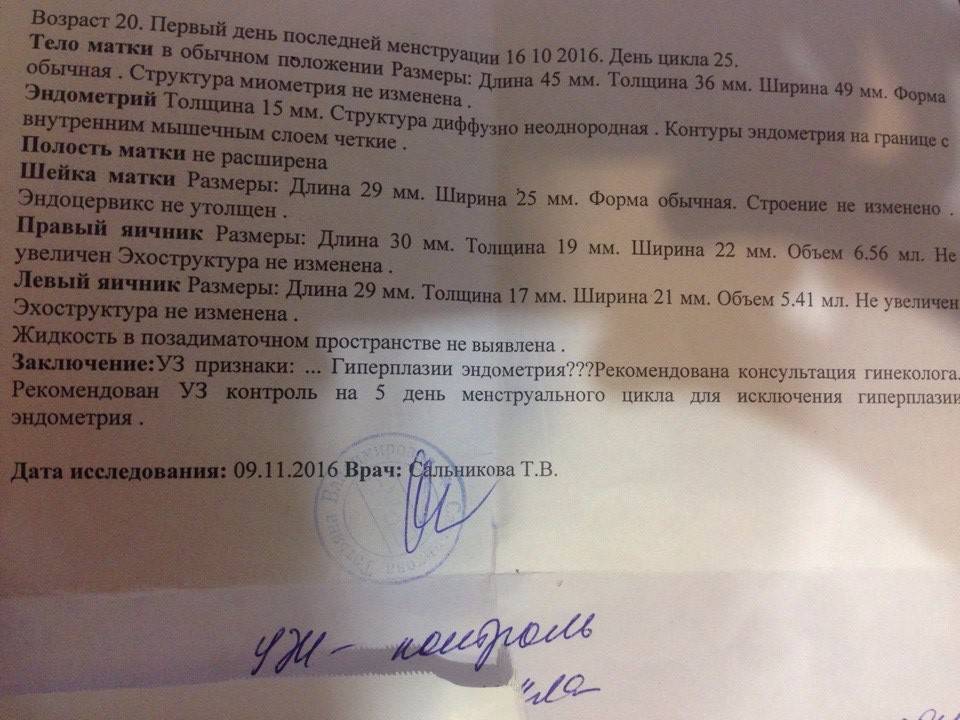

Медицинская диагностика: Гиперплазия эндометрия на УЗИ

Раздел: Мудрость в объективе